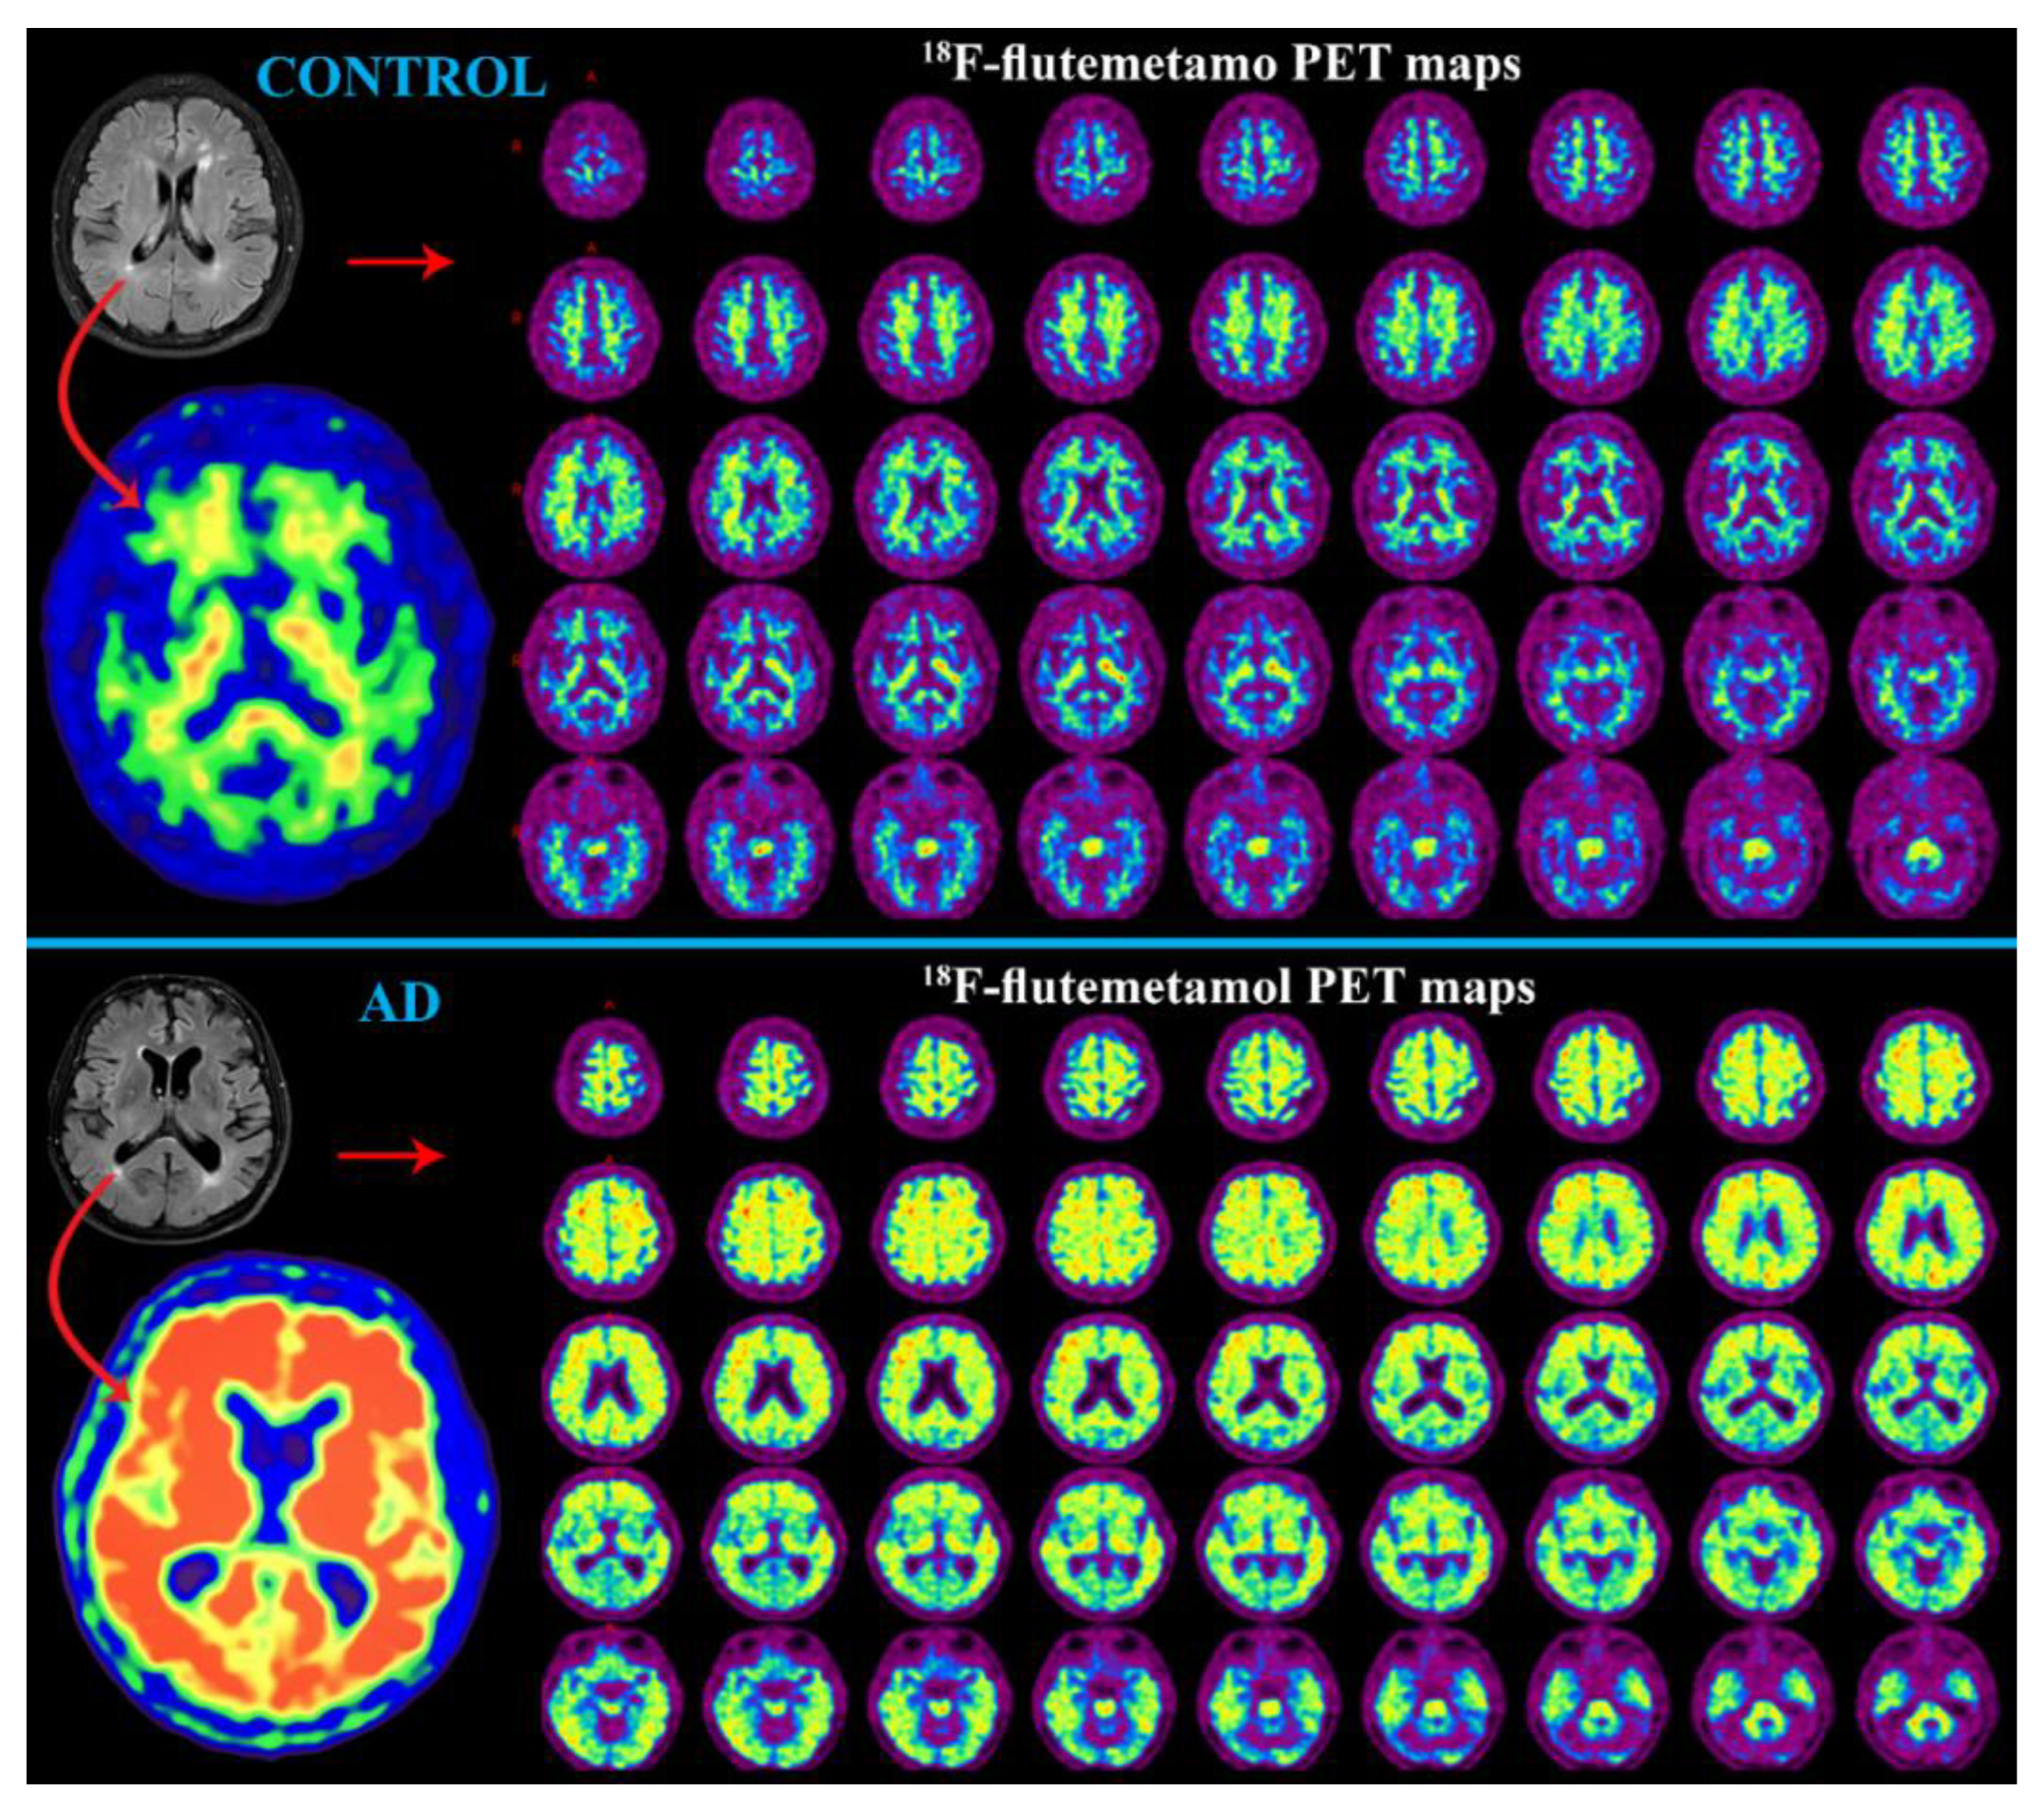

PET with Aβ Radiotracer